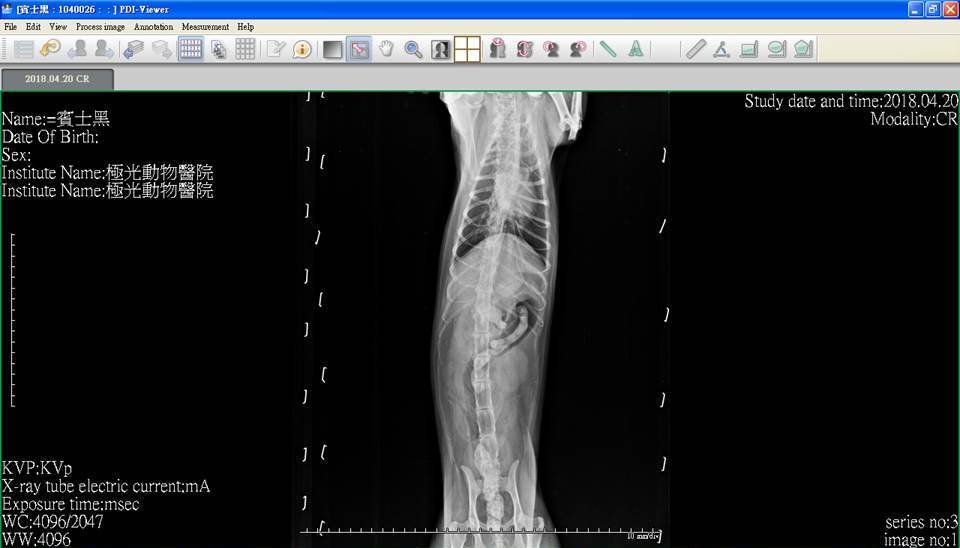

主題: 患有腎衰口炎胰臟炎的麵滷 申請者姓名: 臺北市支持流浪貓絕育計劃協會 花色: 申請日期: 2018-05-08 17:24:45 申請者部落格: 申請者臉書網址: http://admin.tnrtw.org/hospice_add.php 所在縣市/合作醫院: 台北市/極光動物醫院 治療費用: 3600元 需求人數: 8人 已結案 (2024-06-01 13:12:24) 報名人員: 劉小賢(已付款)、林小豬 x2(已付款)、Ed Tsai x5(已付款)、 候補人員: 動物病情說明: 麵滷患有腎衰、嚴重口炎、胰臟炎,這些病症都會讓牠食慾較差,除了吃藥打皮下注射,協會照護員每日都會灌食以維持牠的體力,並每週定期看診做詳細檢查,近日牠因食慾下降更多,精神不好,協會立即安排帶牠就醫,做了血檢及x光,牠的口炎情況變得更嚴重,醫生開了藥希望可以讓麵滷口炎情況好轉,就能恢復些食慾。 動物近況說明: 每週回診、服藥、每日皮下輸液、灌食、給自煮鮮食,希望可以讓牠病情穩定。